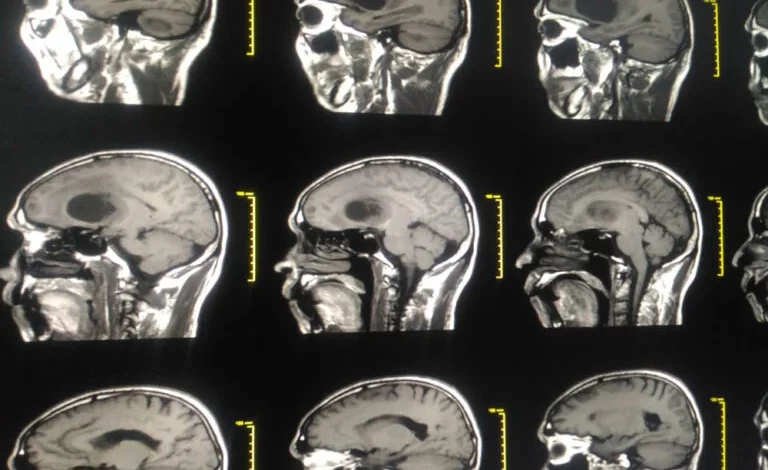

The researchers’ molecule Z4P inhibits one of the mechanisms that regulate protein production in a cancer cell. This inhibition causes the cancer cell to die. Three pictures show the spread of the tumor after 20 days of treatment on mice. Control: Untreated tumor. TMZ: Follow-up treatment solely with chemotherapy. Combo: Combination treatment with chemotherapy and the inhibitor Z4P. Molecule image: X. Guillory, photos from animal studies: D. Pelizzari-Raymundo.